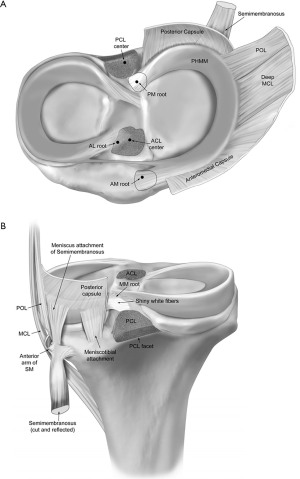

Meniscal root tears were first described in 1991 by Pagnani et al. (1). These tears are currently defined as either a bony or soft tissue avulsion of the meniscal attachment, or as a radial tear within 1 cm of this attachment (2). The medial meniscus (MM) is a crescent-shaped fibrocartilage with a triangular cross-section that covers between 50% and 60% of the medial tibial plateau (3). The MM has much less mobility than the lateral meniscus, in large part due to its attachment to the joint capsule and medial collateral ligament (MCL). The MM is anchored anteriorly and posteriorly to the subchondral bone of the tibia via their respective root attachments (3,4). The MM posterior root (MMPR) attaches posteriorly behind the apex of the medial tibial plateau, 9.6 mm posterior and 0.7 mm lateral to the apex of the medial tibial spine, and 8.2 mm anterior to the most proximal insertion of the posterior cruciate ligament (4,5) (Figure 1). The MM anterior root (MMAR) attaches to the anteromedial proximal tibia, along the intercondylar crest. The center of the MMAR lies 18.2 mm anteromedial to the center of the anterior cruciate ligament (ACL) tibial footprint, 9.2 mm anteromedial to the nearest edge of the ACL footprint, and an average of 7.6 mm anterior to the nearest tibial plateau articular cartilage (5,6). This has been shown to be an average of 9.2 mm anteromedial to the ACL and 27.5 mm anterolateral from the apex of the medial tibial eminence (7).